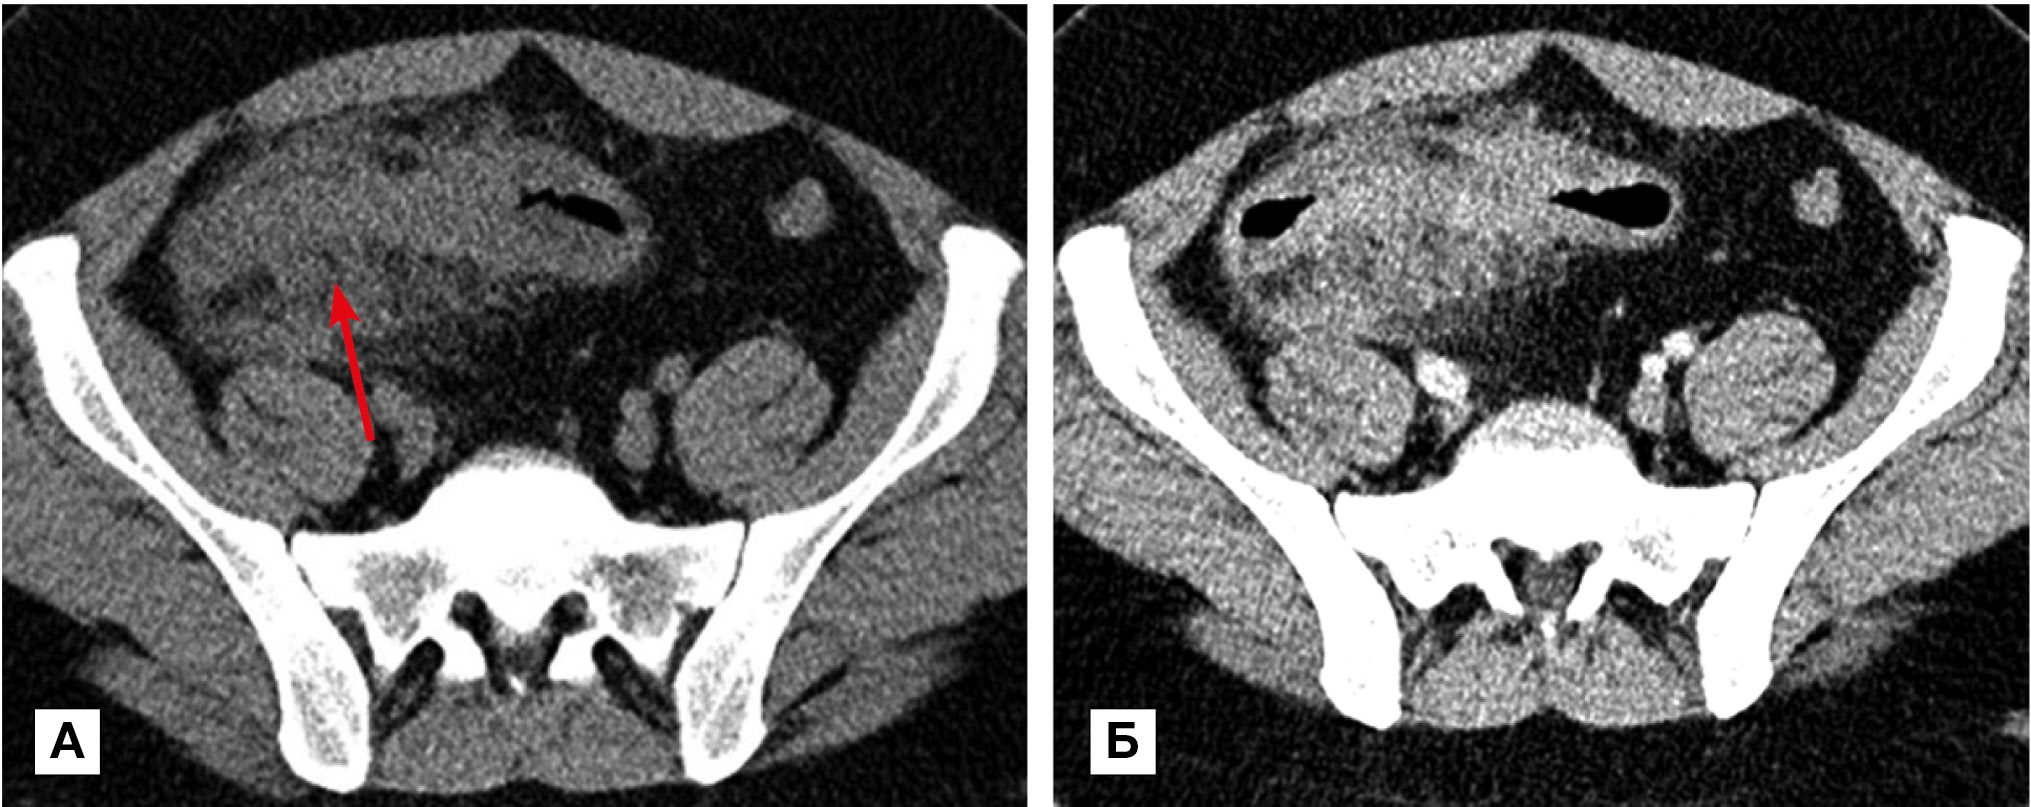

Рис. 2. Больная, 34 года. МСКТ: болезнь Крона, множественное поражение тонкой и толстой кишки. Артериальная фаза контрастного усиления. Фрагменты аксиальных томограмм

Примечание. Определяется сегментарное утолщение стенки ТК (стрелки) и нисходящей ободочной кишки (пунктирная стрелка). При контрастном усилении наблюдается трансмуральное контрастное усиление стенки и усиление сосудов брыжейки (обозначено кругом).

В фазу ремиссии болезни Крона контрастирование стенки характеризовалось трансмуральным утолщением и слоистостью на фоне развития фиброзных изменений в подслизистом слое и повышенного контрастного усиления слизистой оболочки (рис. 3, А) или отложением жировых включений в подслизистом слое (рис. 3, Б).

Рис. 3. МСКТ: болезнь Крона, стадия неполной ремиссии

Примечание. А — артериальная фаза контрастного усиления: определяется трехслойная структура стенки терминального отдела подвздошной кишки (стрелка) за счет развития фиброзных изменений в подслизистом слое и повышенного контрастного усиления слизистой оболочки. Б — больная в возрасте 67 лет: болезнь Крона, стадия ремиссии; нативное исследование: трехслойная структура стенки терминального отдела подвздошной кишки объясняется отложением жировых включений в подслизистом слое (стрелка).